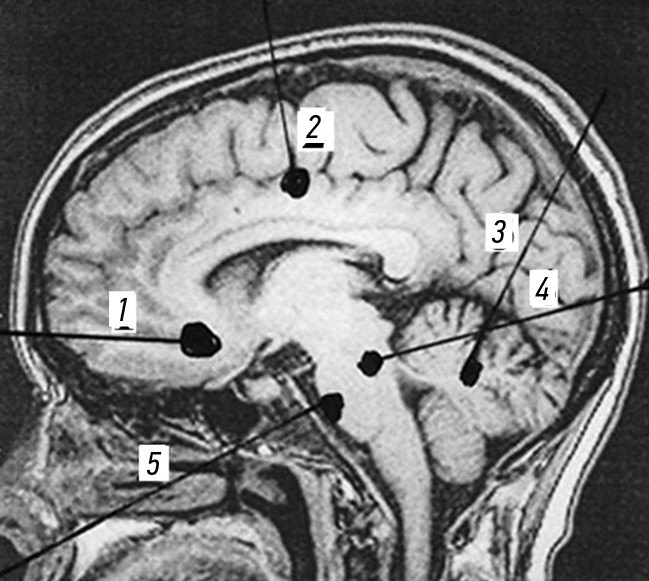

На рис. 2 представлены зоны поражения сосудов ГМ при огнестрельных проникающих черепно-мозговых ранениях.

Рис. 2. Магнитно-резонансная ангиография головного мозга с зонами расположения сосудов: 1 — сосуды подкорковых образований, желудочков и ствола головного мозга; 2 — сосуды коры головного мозга.